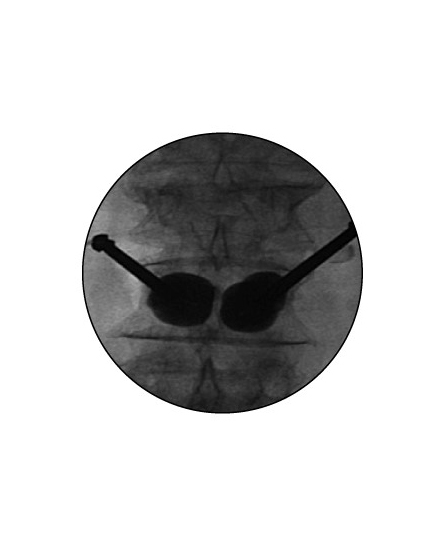

経皮的椎体形成術 BKP(ビーケーピー)

適応となる疾患:骨粗鬆症性椎体骨折、転移性脊椎腫瘍

骨粗鬆症による背骨の骨折や転移性脊椎腫瘍(がんの背骨への転移)による病的骨折に対して世界中で行われている低侵襲な手術法です。日本では2011年に保険適用になり行われています。全身麻酔をして背中の約5mmの傷2カ所から細い針を骨折椎体に挿入します。その針を介して風船(Balloon)を骨折椎体内に設置し、ゆっくりと潰れた骨を整復・復元します。整復後に除去した風船のスペースに骨セメントを注入して、骨折を人工的に接合します。手術は約1時間程度で、手術直後から痛みが軽減することが多く、翌日より起立・歩行を開始します。入院期間は通常約3~7日程度になります。